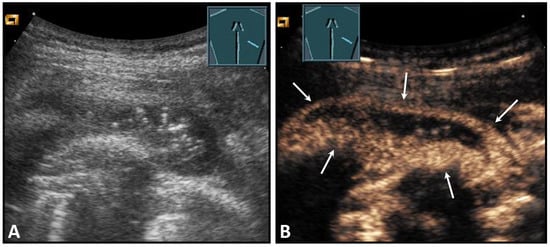

Border shadow artifacts may indicate an apparent diaphragmatic gap, which disappears when the transducer position is changed (Figure 30).

Figure 30.

Illustration of artifact-related apparent diaphragmatic rupture (A, arrow) with regular findings and slightly lateral sound propagation to the diaphragm (B).